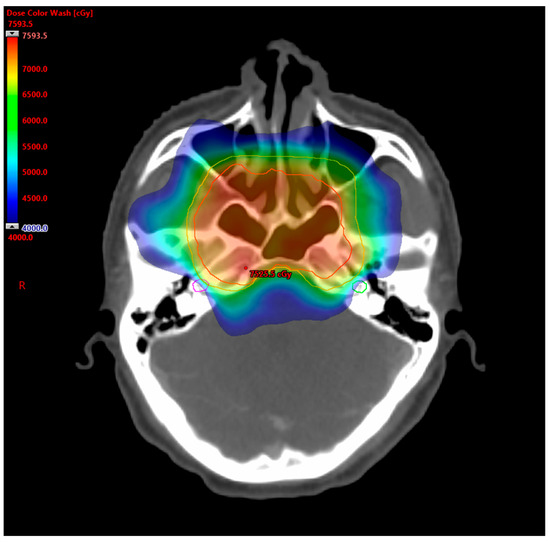

4.3. Selection of Radiotherapy Techniques

- Gao, J.; Qian, T.L.; Tao, C.Z.; Zhang, Y.H.; Zhou, Y.; Yang, J.; He, J.; Wang, R.; Zhou, P.J. SmartArc-based volumetric modulated arc therapy can improve the middle ear, vestibule and cochlea sparing for locoregionally advanced nasopharyngeal carcinoma: A dosimetric comparison with step-and-shoot intensity-modulated radiotherapy. Br. J. Radiol. 2015, 88, 20150052. [Google Scholar] [CrossRef]

- He, L.; Xiao, J.; Wei, Z.; He, Y.; Wang, J.; Guan, H.; Mu, X.; Peng, X. Toxicity and dosimetric analysis of nasopharyngeal carcinoma patients undergoing radiotherapy with IMRT or VMAT: A regional center’s experience. Oral Oncol. 2020, 109, 104978. [Google Scholar] [CrossRef]

- Lamaj, E.; Vu, E.; van Timmeren, J.E.; Leonardi, C.; Marc, L.; Pytko, I.; Guckenberger, M.; Balermpas, P. Cochlea sparing optimized radiotherapy for nasopharyngeal carcinoma. Radiat. Oncol. 2021, 16, 64. [Google Scholar] [CrossRef] [PubMed]

- Nanda, S.; Parida, S.; Ahirwar, M.K. A Dosimetric Comparison of Volumetric-modulated Arc Therapy and IMRT for Cochlea-sparing Radiation Therapy in Locally Advanced Nasopharyngeal Cancer. J. Med. Phys. 2023, 48, 248–251. [Google Scholar] [CrossRef] [PubMed]